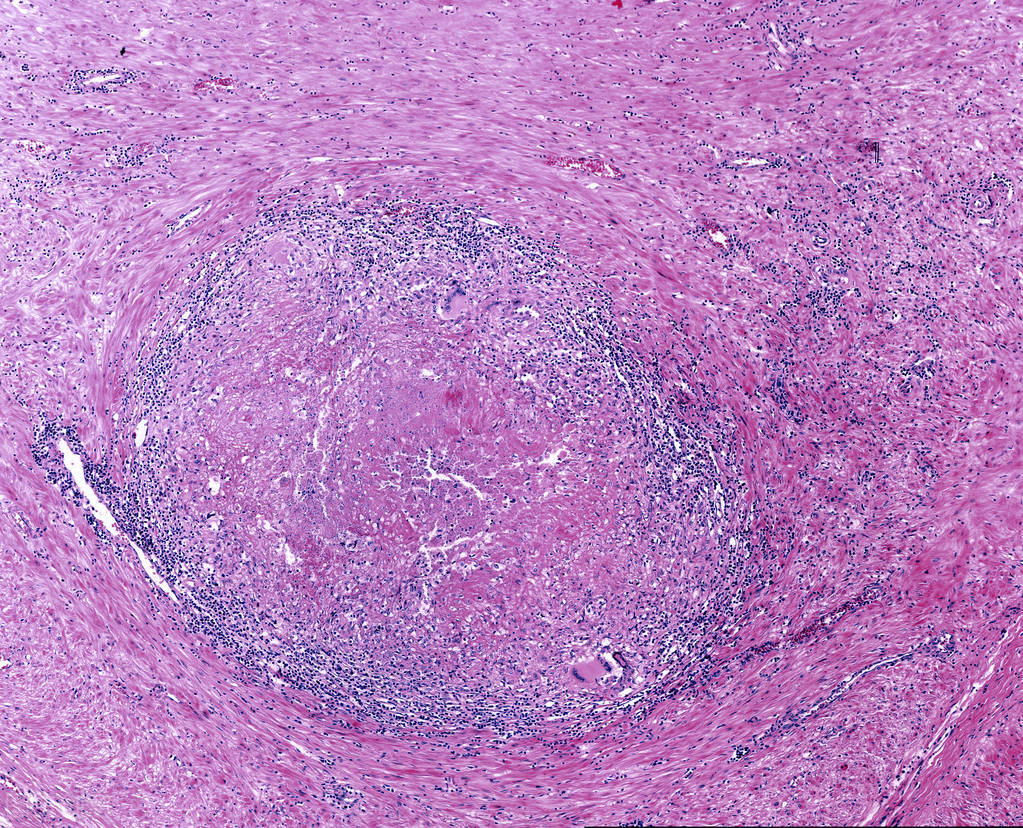

而这里就不得不提一提人体的巨噬细胞了,这是我们体内一种很重要的细胞,是人体免疫系统的先锋军,可是与其他细胞不同的是,他不是很能干,只有当它占据了绝对的优势时,才能够消灭感染,不然的话,可能会成为结核杆菌生存繁衍的温床。

结核菌有很多手段来躲避巨噬细胞,它本身就能够抑制巨噬细胞的生长,使其变成适合自己生存的环境。同时还可以抑制巨噬细胞产生活性氧,活性氧是巨噬细胞杀灭结核杆菌的主要手段,它如此多的手段,能够安安稳稳的生活在我们人体内。